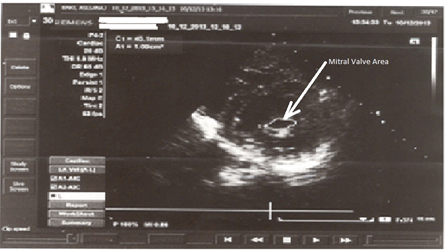

The patient was treated with oral anticoagulants (acenocumarol), beta-blockers (atenolol), and diuretics (hydrochlorothiazide plus spironolactone). Coronary angiography which showed a 75% stenosis of the right coronary artery (Figure 2).

Figure 2: Coronary Angiography. Left anterior oblique caudal (spider) view. The image shows a 75% proximal stenosis of the right coronary artery. The stenosis in mechanical due to compression of the artery between aorta and pulmonary artery.